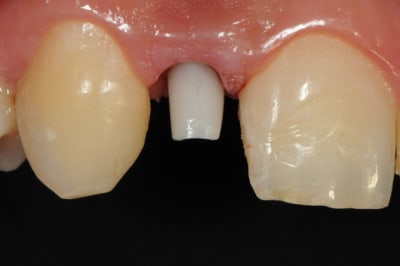

01/09/2010 à 16h28

-cicatrisation de la première vis de cica,

-diamètre plus gros pour la vis de cica

- pilier pour la provisoire

- provisoire moule ION

- ajustage

- polissage soigneux

la suite tout à l'heure, ça sonne à la porte...